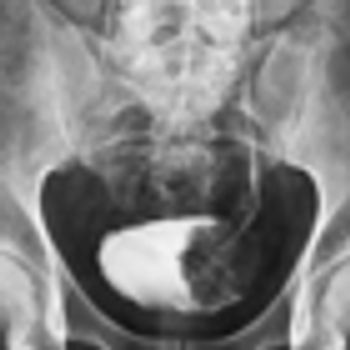

A 55-year-old woman with a history of metastatic melanoma in remission for 8 years presented to the emergency department with gross hematuria. A CT scan, ordered because the patient was in menopause, demonstrated a bladder tumor.